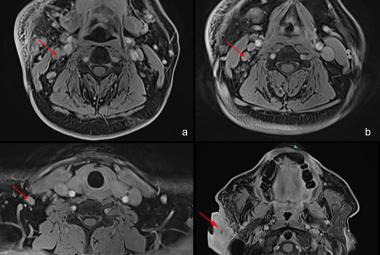

Iatrogenic tracheal injury (ITI) can occur in operations, intubation or tracheobronchial endoscopy. ITI associated with hemithyroidectomy is a very rare but devastating complication which can manifest immediately or in a delayed manner. The therapeutic approach can be conservative or surgical, but there is no universal consensus on the management. In this article, we described a rare case of intra-operative tracheal injury involving the cricothyroid membrane and right posterolateral first to second tracheal rings during right hemithyroidectomy, in which primary suturing was attempted. However, on the sixth day postoperatively, the patient developed neck swelling and respiratory distress owing to infection at surgical site complicated with temporary vocal cord palsy, which necessitated a tracheostomy. Patient was subsequently managed successfully with conservative management. We concluded that the therapeutic approach of ITI should be based on the time of presentation, clinical condition of the patient, size and location of the lesion.

FIGURE 1: Neck re-exploration revealing intact suture at the site of primary repair